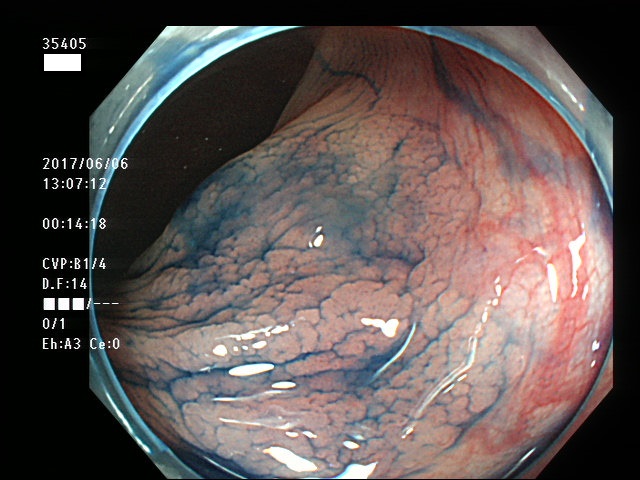

上記100名より抽出した平坦・陥凹型腺腫・SSAP(=癌化の危険が高いが見落としやすい病変)の内視鏡写真

35403 35404 35405 35409 35410 35412 35413 35414 35416 35417 35418 35419 35420 35421 35426 35429 35430 35433 35434 35435 35438 35439 35440 35444 35445 35447 35449 35450 35451 35452 35453 35454 35458 35460 35463 35464 35466 35468 35469 35470 35472 35473 35478 35479 35481 35483 35485 35489 35490 35491 35492 35493 35498 ・・・・・の54名